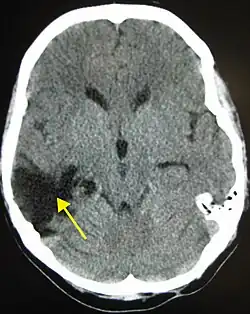

One of the top causes of death worldwide, strokes are disruptions of the blood supply to the brain. These disruptions can be triggered by a variety of ways, the most common of which are the rupturing of an artery (or hemorrhage), or blockages, which may either by from clots or other obstructions. Whatever the immediate cause, obstruction of the vascular system delivering blood to the brain can quickly lead to the death of cells in the affected areas. Like traumatic brain injury, the exact symptoms and consequences of a stroke depends on the region most affected, however there are some common characteristics. Paralysis or weakness on one side of the body- usually manifested in slurring of speech or drooping of the face- is very common since usually the blocked artery will be responsible for delivering blood to one specific brain hemisphere.